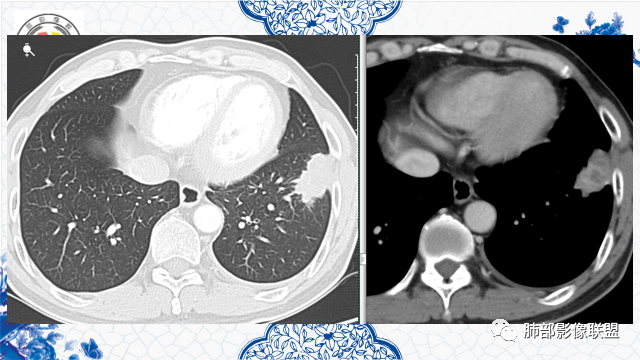

有胃肾恶性肿瘤手术史。左肺下叶胸膜下不规则肿块,部分边缘平直、部分膨隆,近端见支气管进入后截断,增强后不均匀强化,可见低密度坏死无强化,边缘见边界清楚的GGO,考虑恶性肿瘤——肺腺癌可能性大。鉴别转移瘤、鳞癌。

左下叶不规则实变,有平直及u型凹陷,胸膜糊墙,不均匀强化,其内可坏死灶,肿块内缘起始部可见钙化灶,病史较长,虽有胃肾肿瘤史,但影像表现及病灶走行(爬行征)均不支持转移,综合分析考虑炎性肉芽肿,OP并脓肿,其次考虑TB,留个尾巴鉴别腺癌

增强坏死周围似乎见环形强化的环

第三,强化有环形强化的感觉,坏死区太圆太规整。